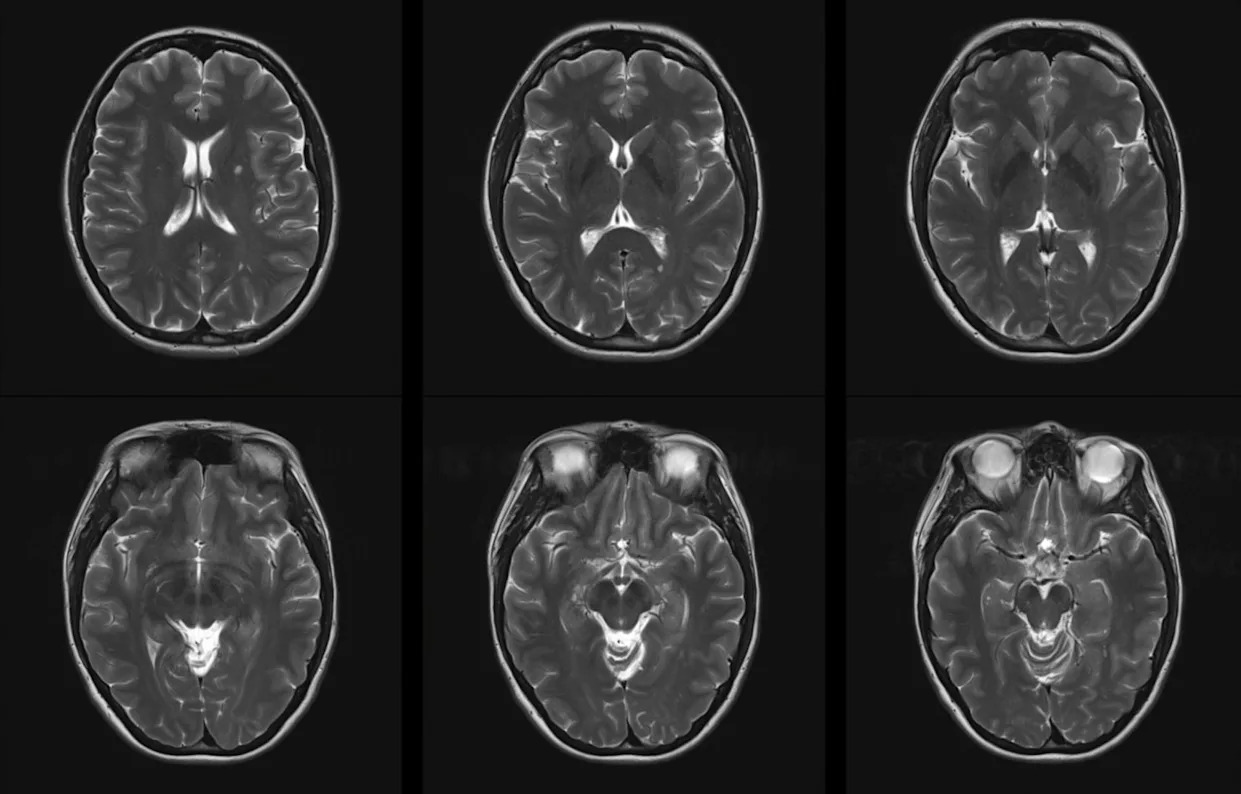

Air pollution's reputation as a "silent killer" is well-earned. New research indicates that dirty air is also linked to raising the risk of developing multiple sclerosis and worsening the disease for those already suffering from it. Multiple Sclerosis News Today wrote about a new study published in the Annals of Clinical and Translational Neurology that explored the relationship between air pollution and MS. The review analyzed 22 studies involving over 16 million people and looked at pollutants such as particulate matter as well as airborne chemicals such as carbon monoxide and sulfur dioxide. Researchers found a 21% increased risk of MS with long-term exposure to fine particulate matter with diameters under 2.5 micrometers (aka PM2.5) and a 20% increase for slightly larger particles of under 10 micrometers. No significant association for developing MS was found for other pollutants, such as carbon monoxide and sulfur dioxide. People already contending with MS weren't so lucky. Short-term exposure to particulate matter and all of the other pollutants was linked to at least one, if not all, of the negative impacts like lesions, worsening disease, or heightened relapse risk. Public health experts stress the importance of cleaner air, and this study provides even more backing for that mission by illuminating a worrisome relationship between air pollution and MS. "Our study provides strong evidence of the association between air pollution and risk of developing MS and severity of MS including relapses, developing CELs [contrast-enhancing lesions], and disability progression," the scientists wrote. MS is a devastating disease impacting 2.8 million people worldwide, including many young adults. The disease creates an economic burden of over $85 billion in the U.S., per the study. Air pollution is a worldwide problem affecting 99% of the global population, according to the World Health Organization. It says that is responsible for nearly 7 million premature deaths annually. Which of these savings plans for rooftop solar panels would be most appealing for you? Save $1,000 this year Save less this year but $20k in 10 years Save less in 10 years but $80k in 20 years Couldn't pay me to go solar Click your choice to see results and earn rewards to spend on home upgrades. Events like wildfires and persistent smog can lead to dangerous conditions for residents to breathe in. These conditions' links to MS add even more reason to be wary of polluted air. Efforts to improve air quality, such as increasing the use of electric vehicles, are ongoing. Studies in California show a major reduction in pollutants through EV adoption. Other measures, such as the Clean Air Act in the U.S., are in place to protect citizens from polluted air from industrial sources. Getting away from energy sources that add more pollution to the air, like oil and gas, is another important move. The movement toward wind and solar power can help clean the air over time. Get TCD's free newsletters for easy tips to save more, waste less, and make smarter choices — and earn up to $5,000 toward clean upgrades in TCD's exclusive Rewards Club.